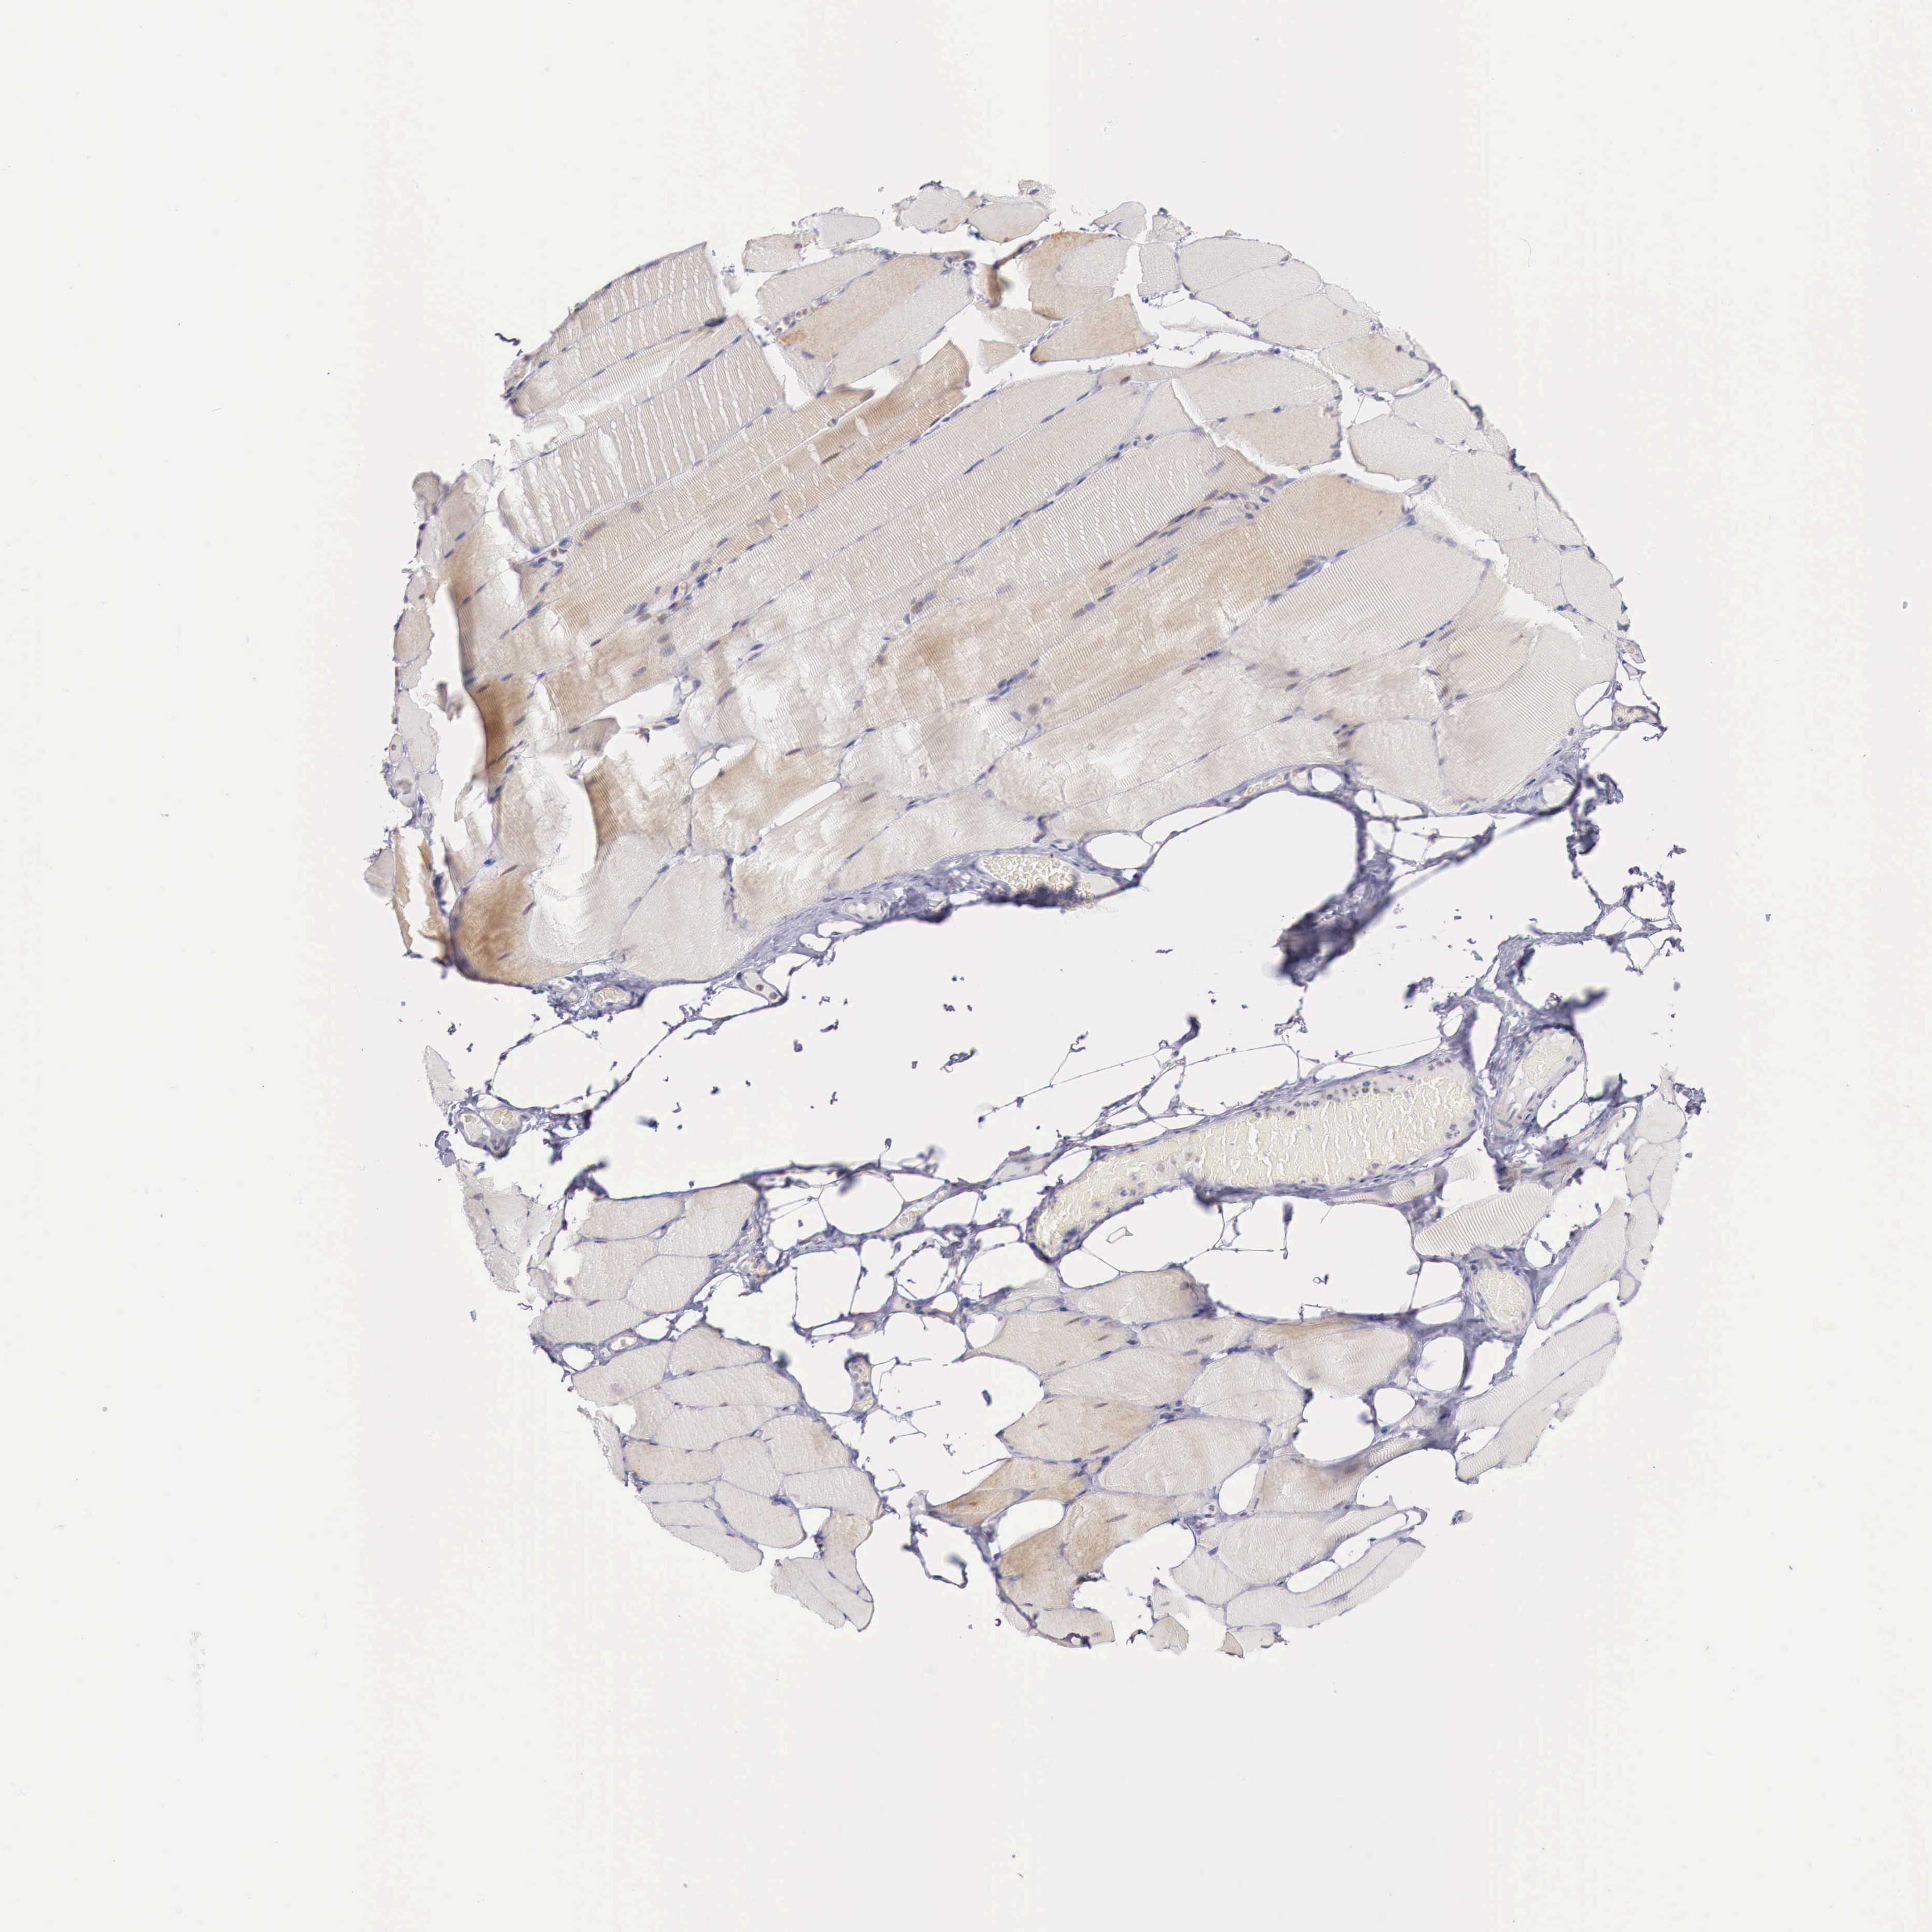

SKELETAL MUSCLE - Antibody stainingi

Antibody staining in the annotated cell types in the current human tissue is reported as not detected, low, medium, or high, based on conventional immunohistochemistry profiling in selected tissues. This score is based on the combination of the staining intensity and fraction of stained cells.

Each image is clickable and will lead to virtual microscopy that enables deeper exploration of all samples and also displays staining intensity scores, fraction scores and subcellular localization as well as patient and tissue information for each sample.

Antibody HPA000367

Myocytes Low